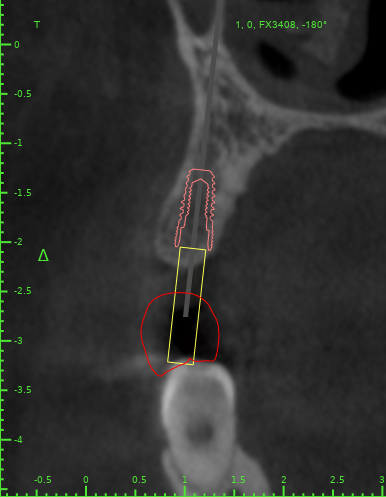

Женька Опубликовано 13 декабря, 2021 Поделиться Опубликовано 13 декабря, 2021 Как считаете, возможно такая позиция имплантата? Ссылка на комментарий

Doc Опубликовано 13 декабря, 2021 Поделиться Опубликовано 13 декабря, 2021 С точки зрения хирурга может и пройдет, а вот ортопед материться будет. Там коронку воткнуть будет нелегко. 1 Ссылка на комментарий

Женька Опубликовано 13 декабря, 2021 Автор Поделиться Опубликовано 13 декабря, 2021 @Doc вот как раз на этот счёт и погляжу пациента в субботу мне тоже кажется, что зуб то не проходит... Что предложили бы такому пациенту, Док? Ссылка на комментарий

Doc Опубликовано 13 декабря, 2021 Поделиться Опубликовано 13 декабря, 2021 1 минуту назад, Женька сказал: @Doc вот как раз на этот счёт и погляжу пациента в субботу мне тоже кажется, что зуб то не проходит... Что предложили бы такому пациенту, Док? Ну, тут прикуса толком не видно, поэтому сложно сказать. Но в такой ситуации либо ортодонтия, либо будет узкая страшненькая короночка с большими поднутрениями для хранения пищи. Ссылка на комментарий